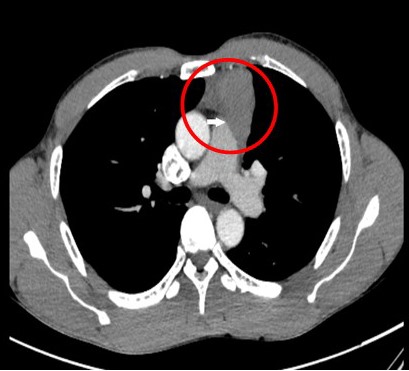

Kết quả chụp CT scanner ngực cho thấy hình ảnh khối u trung thất trước (Vùng khoanh tròn màu đỏ)

Ông Lê Văn M., 47 tuổi, trú tại xã Tràng Lương, thị xã Đông Triều. Khoảng nửa năm nay ông thường hay ho khan, tức ngực, khó thở. Tuy nhiên ăn ngủ vẫn bình thường, không gầy sút cân, không có biểu hiện của bệnh nhược cơ. Tháng 11-2020, ông M. đi khám tại Trung tâm Y tế thị xã Đông Triều, sau chụp cắt lớp vi tính cho kết quả u trung thất trước và được chuyển Bệnh viện Việt Nam - Thuỵ Điển Uông Bí điều trị. Qua thăm khám, làm các xét nghiệm cần thiết, người bệnh được chẩn đoán u trung thất trước, có chỉ định phẫu thuật cắt bỏ khối u và tuyến ức.

Các bác sĩ khoa Phẫu thuật - Can thiệp tim mạch & Lồng ngực Bệnh viện cho biết, trường hợp người bệnh M. khối u đã tiến triển ở giai đoạn muộn. Khối u lớn lệch trái, dạng đặc, bờ chia thùy múi, đè, xâm lấn vào màng phổi trái khiến người bệnh ho khan, tức ngực, khó thở. Người bệnh đã được lựa chọn đường mổ ½ giữa xương ức kết hợp mở ngực trái để cắt u và tuyến ức. Với đường mổ này thì phẫu trường rộng rãi đảm bảo lấy được u và tuyến ức triệt để, an toàn, đồng thời giảm thiểu tổn thương xương ức, giúp người bệnh hồi phục sớm sau mổ. Sau 2 giờ phẫu thuật, các bác sĩ đã lấy bỏ thành công khối u và tuyến ức kích thước 11x5cm cho người bệnh, gửi làm giải phẫu bệnh. Kết quả xác định u tuyến ức tuýp B2 giai đoạn Masaoka II, được chỉ định xạ trị tiếp sau mổ.